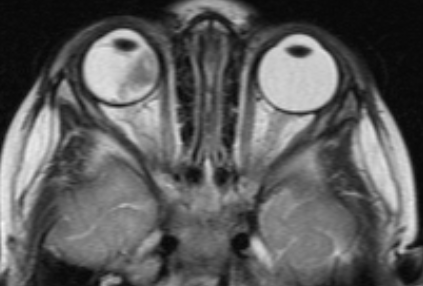

- В - остальные опухоли, располагающиеся отдельно, ограниченные сетчаткой с вероятным наличие субретинальной жидкости в не более чем 3 мм от основы опухоли, не сопровождающееся субретинальным обсеменением (рис. 2).

![Визуализация ретинобластомы с помощью МРТ. Клиническая группа В]()

Рис. 2. Визуализация ретинобластомы с помощью МРТ. Клиническая группа В